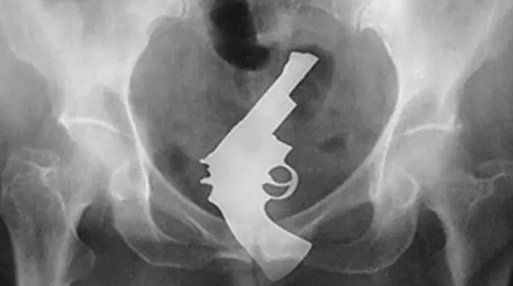

あけすけに言わせてもらえば、bl、そこは入口じゃないし入るわけないやろって冷静にフィクションとして捉えてるんだけど、こういう事実を見ると現実味を帯びてくるな……うーんでも信じられんな……ビデオテープあるやん……やっぱり合成かなぁ………